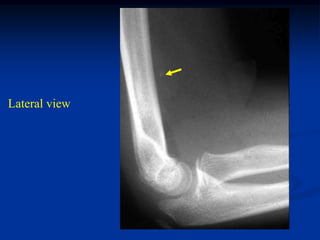

phlebolith

8 year female with

hemangioma distal arm

Lateral view

Coronal T-1 MRI   Coronal T-2 MRI